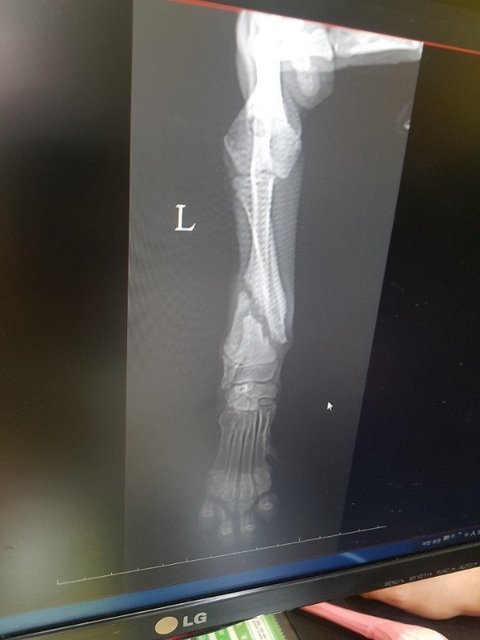

4남매가 보호소 들어와 3마리가 입양가고 혼자 남아 서럽게 울던아이를 구조해 검진결과 앞다리 골절..파보코로나 양성이 나와 연휴내내 입원치료를 했습니다

다행히 다리는 스스로 잘 아물고 있어 수술을 하지않아도 됐습니다